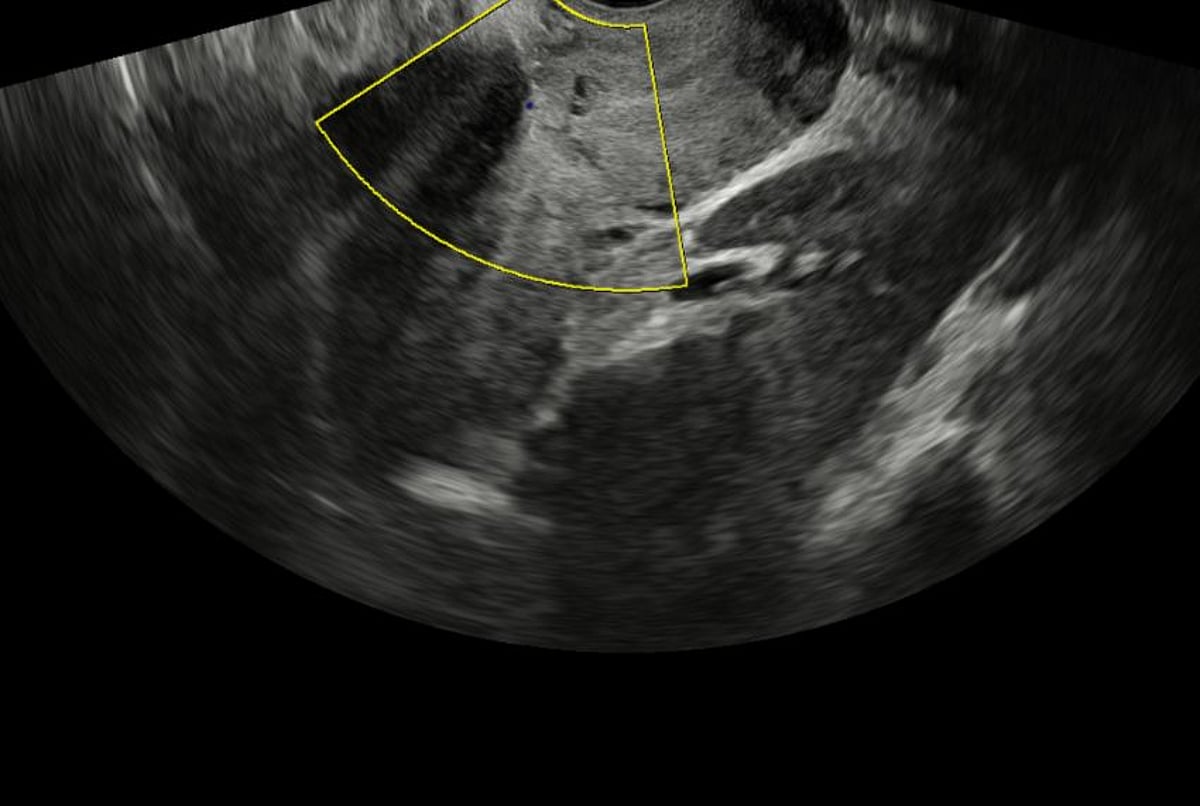

يؤكد الأطباء في مستشفى المانع على أهمية الكشف المبكر عن حالات الحمل عالية الخطورة مثل المشيمة المنزاحة المصحوبة بالتصاق المشيمة. المتابعة الدورية للحمل، وإجراء الفحوصات بالموجات فوق الصوتية، يمكن أن يساعد في تحديد هذه الحالات في وقت مبكر، مما يسمح للفريق الطبي بوضع خطة علاج مناسبة.

وصلت الأم إلى مستشفى المانع وهي تعاني من نزيف مهبلي حاد وآلام شديدة في البطن. بعد إجراء الفحوصات اللازمة، أكد الفريق الطبي تشخيص المشيمة المنزاحة المصحوبة بالتصاق المشيمة. هذه الحالة تتطلب تخطيطًا دقيقًا وفريقًا طبيًا متكاملًا يضم أطباء التوليد، وأطباء التخدير، وفنيي العمليات، بالإضافة إلى وحدة عناية مركزة للأم والجنين.